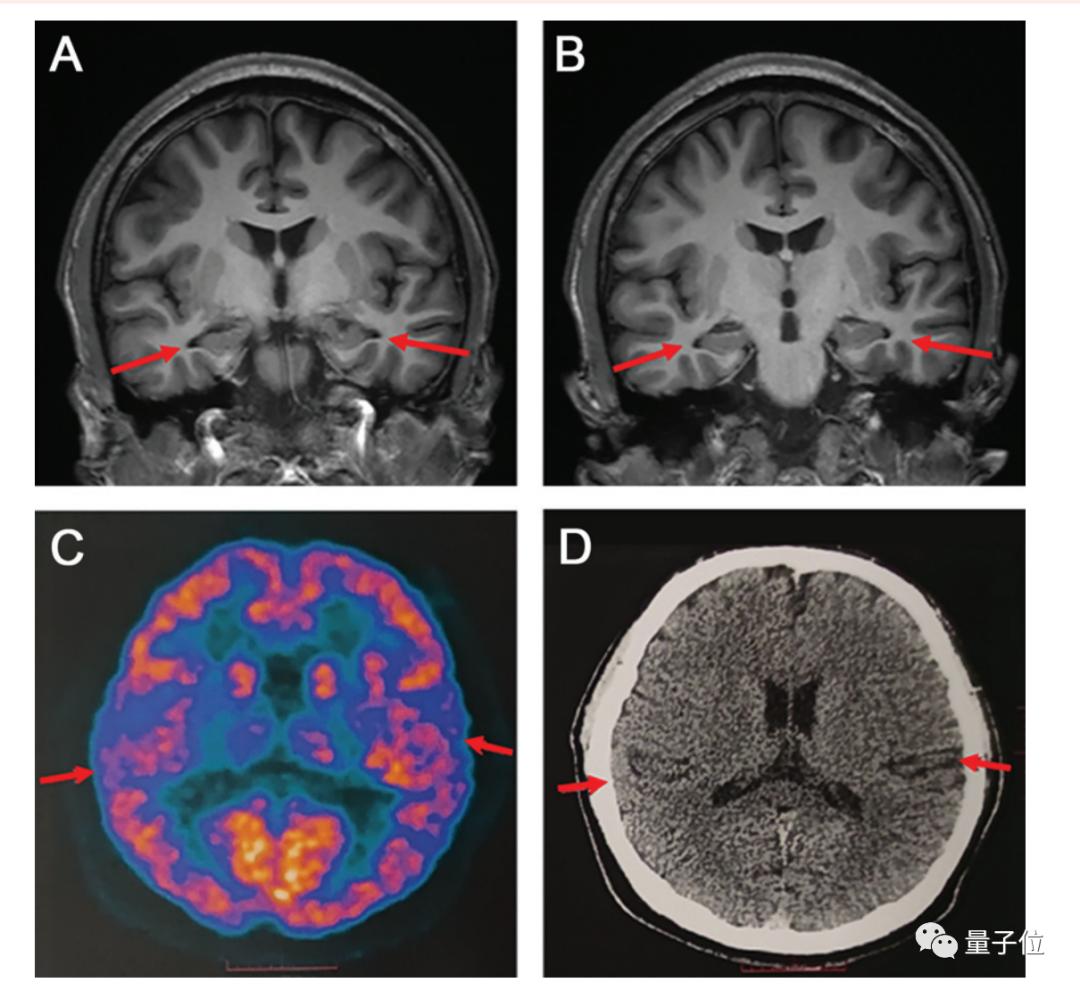

随后,医生们对男孩的大脑进行了核磁共振扫描,结果显示:其双侧海马体轻度萎缩,双侧颞叶也轻度萎缩,代谢水平低下。

要知道,海马体可是是人类大脑的重要结构,负责存储和加工记忆信息。

而颞叶则和语言、注意力、认知加工等功能都有关;颞叶萎缩,除了可能导致语言、注意力和记忆障碍;还可能导致情绪障碍、空间定向障碍等等。

另外,他们还检查了男孩的脑脊液,结果显示:p-tau181蛋白浓度增加,淀粉样蛋白-β 42/40比例降。

综合各检查结果表示,这个少年确实患上了阿尔茨海默症。